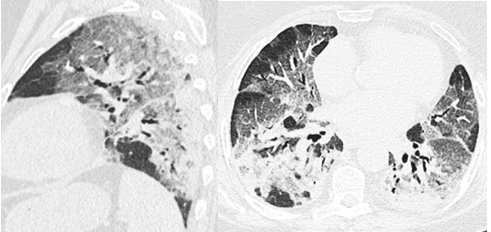

A thoracic CT scan performed on March 29, 2022 revealed ground glass lesions reaching 40% of the lung parenchyma (Figure 1). In view of these lesions and the worsening respiratory distress, the patient was referred to us on March 30, 2022 for specialized management of her SARS-COV-2 respiratory infection. On admission, the patient presented with respiratory distress, asthenia, and a fever of 38.4ºC. However, the patient did not report any significant pathological history.

Figure 1 Axial (right) and sagittal (left) sections in the parenchymal window without contrast injection, showing bilateral asymmetric ground-glass areas, mainly subpleural, some of which are crazy paving associated with localized condensation and bronchiectasis.